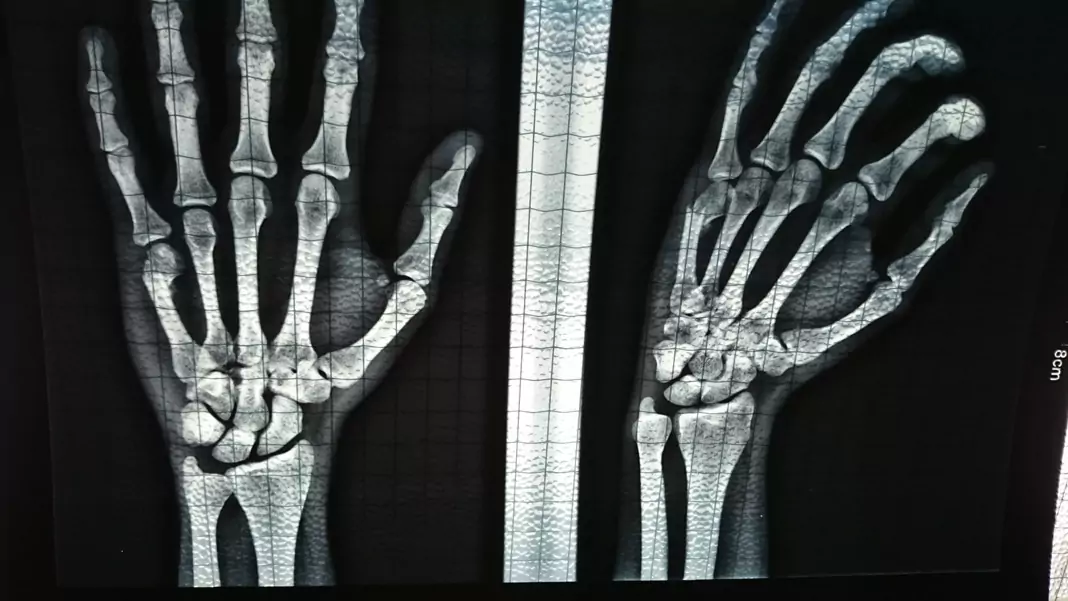

Ревматизъм е неприятно заболяване, от което страдат мнозина. То представлява възпаление на ставите и съединителните тъкании.

Ревматизма може да повлияе негативно върху бъбреците, кожата, сърцето и костите.